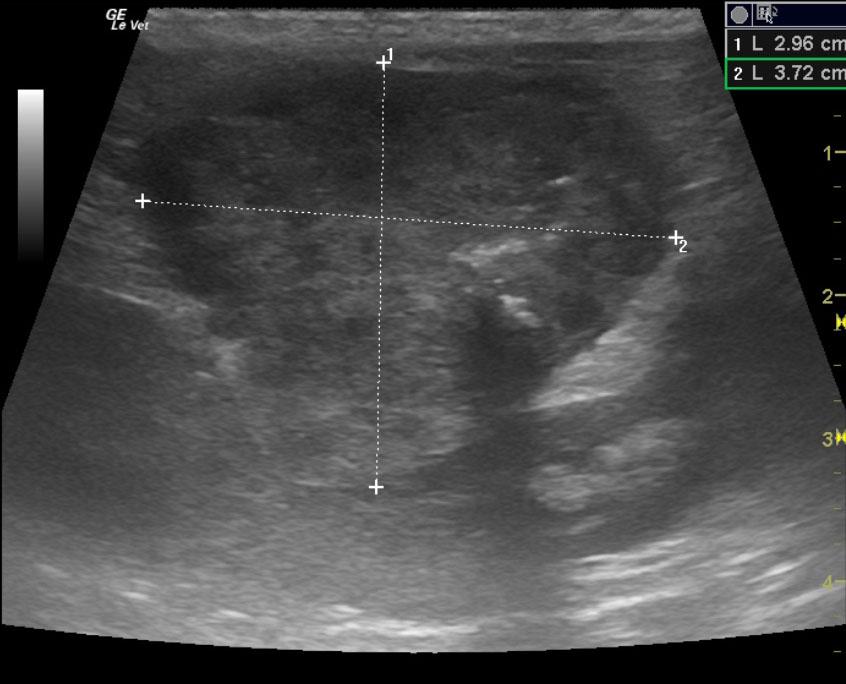

An 16 year-old NM DSH was presented for evaluation of small kidneys and an abdominal mass. Urinalysis showed an inappropriate urine specific gravity (1.014). CBC was within normal limits but elevated creatinine was present on serum biochemistry.